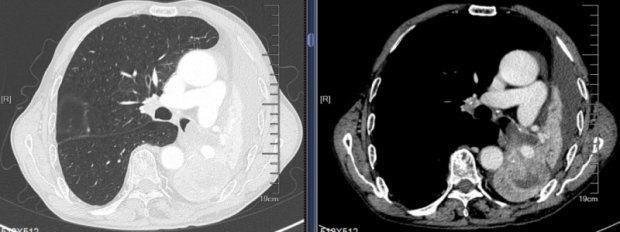

医疗动态 | 徐州一院呼吸与危重症医学科:“镜”下手术显神通,“瘤”去呼吸变轻松

近日,74岁的权先生(化名)因咳嗽、憋喘1个月在外院胸部CT检查提示左肺下叶占位性病变伴有肺不张,行气管镜检查未明确诊断,几番周折后来到徐州市第一人民医院呼吸与危重症医学科...

医疗护理

2024.08.21

阅读 5404